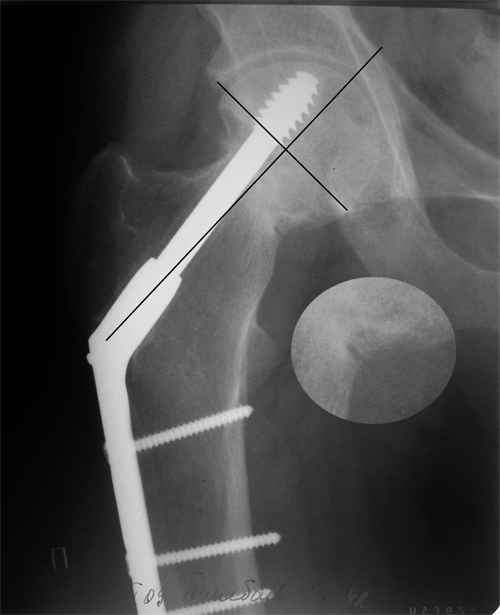

Псевдоартроз шейки правого бедра

Больной Т. 1966 г.р. Травма 28.06.2007. Прооперирован в г. Бишкек, Оп: Остеосинтез правого бедра системой DHS. В последующем беспокоили периодические боли в правом тазобедренном суставе с иррадиацией в коленный сустав в область передней поверхности правого бедра. Лечился амбулаторно с незначительным эффектом.

В 07.04.2008 по 08.05.2008 года лечился в госпитале ГУВД и СО в стационаре с Срастающийся перелом шейки правого бедра в условиях фиксации системой DHS – боли уменьшились. Боли обострились 03.02.2009 внезапно, госпитализирован.

Результат - Псевдоартроз шейки правого бедра (имеются косвенные признаки разрушения спонгиозной части головки бедра) Планируется - Работает милиционером. Имеющийся опыт протезирования у данной категории во всех случаях в ближайшее время заканчивался дисквалификацией.

Работоспособный возраст (43 года). Наиболее приемлемым и реальным методом лечения предполагается: Удаление конструкций из бедра. Заполнение полости от винта монолитным аутотрансплантатом из крыла (крылев) подвздошной кости. Медиализация большого вертела. Предполагаемый период нетрудоспособности 3-4 мес.